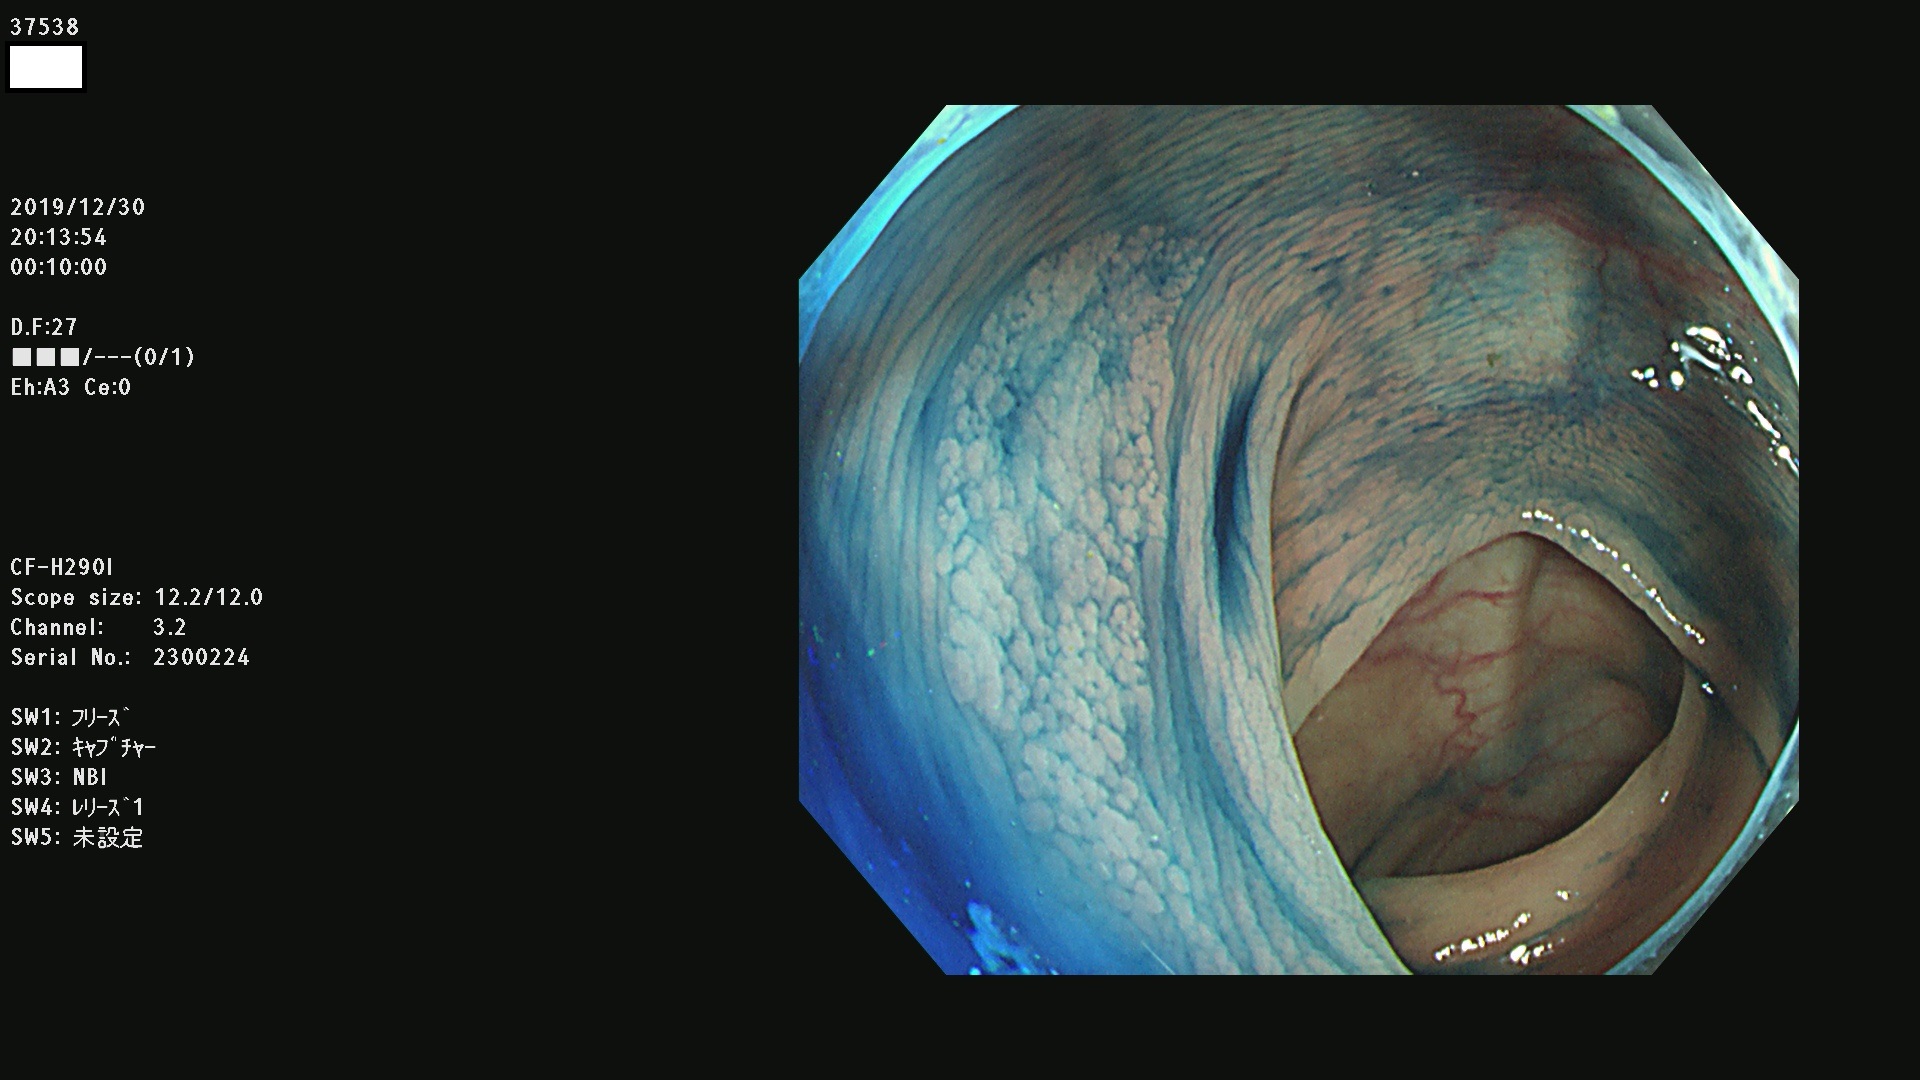

発見困難で危険性の高い平坦型病変(上記100名より抽出) ![]()